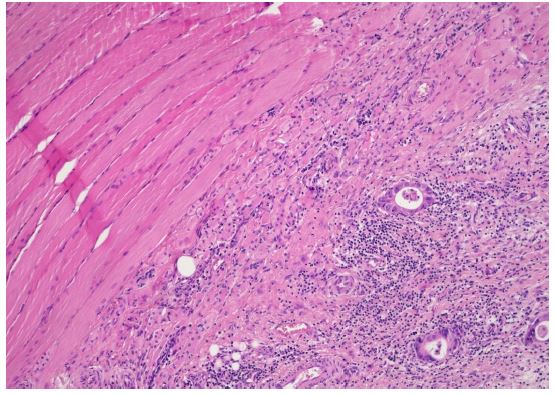

An abdominal Computed Tomography (CT) scan discovered a dilated colon up to the splenic flexure. A CT scan did not show regional nor distant metastases. Subsequently, the patient underwent exploratory laparotomy, which showed an obstructive tumour in the middle of the transverse colon, and there were no signs of macroscopic metastases in the abdominal cavity. The patient underwent resection of the transverse colon with end-to-end anastomosis. Postoperatively, the patient recovered well. Histopathological examination of the specimen revealed a moderately differentiated tubar adenocarcinoma, irregularly infiltrating the serosa, without lymphovascular invasion (Figure 1a), (T4a) and without nodal involvement (11 negative pericolic and 1 negative mesenteric lymph nodes were found); pT4a, N0, M0 (stage IIA); R0 resection was performed. Microsatellite instability-high (MSI-H) cancer was not proven.

Figure 1a: Microscopic histological findings. A resected specimen of the sigmoid colon showed an irregular ulcerated lesion. A histological examination of the resected specimen of the sigmoid colon revealed a moderately differentiated adenocarcinoma invading the subserosal layer. (×100 magnification; haematoxylin and eosin stain).